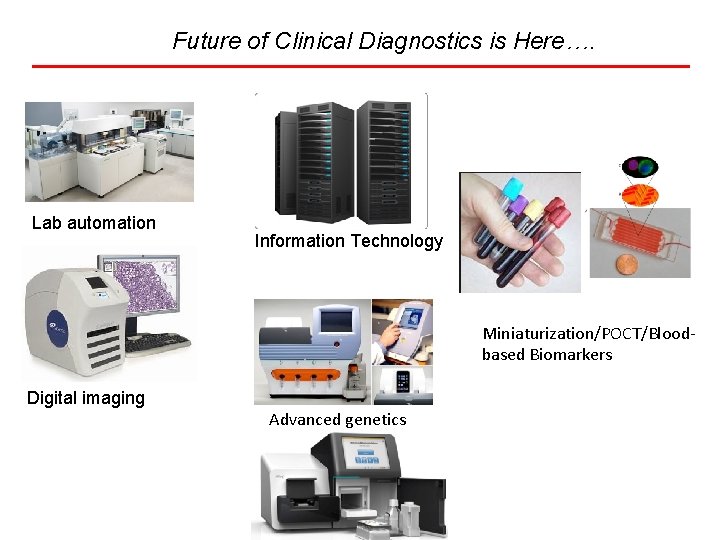

Future of Clinical Diagnostics is Here…. Lab automation Information Technology Miniaturization/POCT/Bloodbased Biomarkers Digital imaging Advanced genetics